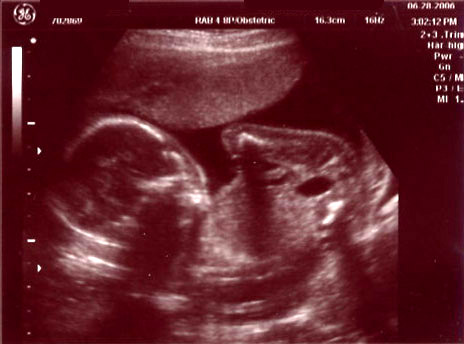

| June 28, 2006 - Twenty Week Ultrasound: IT'S A BOY!!! |

Today was probably the

longest day of my life having to wait for our 3:00pm appointment. I

went to work today, but didn't get much done since I was so excited to

finally find out what we were having. We got to the doctor's and they

took us right away. Within 44 seconds of the technician turning on the

ultrasound machine, she showed us the picture of the legs spread wide open

and it was obvious that we were having a boy!! He was so active

throughout the entire ultrasound, kicking and turning all over the place.

He is absolutely beautiful!!! I am in love with him already. He

weighed 13.5 ounces and he is perfect and healthy!! We are so excited

to start planning the nursery for our little man. Here are the

ultrasound pics from today. Enjoy!! ~Jen

Another profile shot |